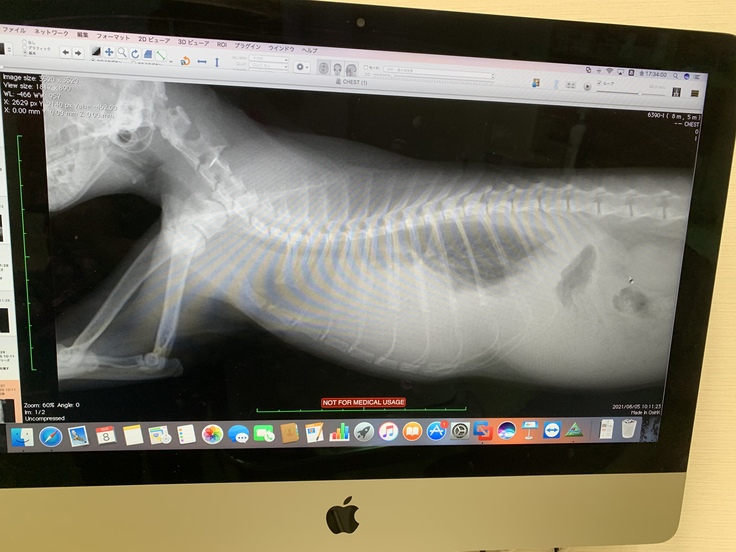

念の為レントゲンで胸水・腹水の有無確認

【9月18日~】

体の火照りに気づき、病院で測ったところ40.1度の熱が出ていました。

また、食欲もなくなり、基本寝ていることが多くなっていきます。

ついに今の治療では進行が抑えられない状態になってしまいました。